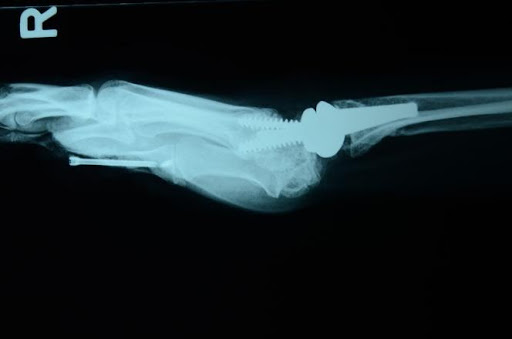

Aşağıda gösterildiği gibi, instabiliteyi sabitlemek için volar ve dorsal ligamanın skafolunatını tendon grefti ile yeniden yapılandırmak genellikle tercih edilen prosedürdür.